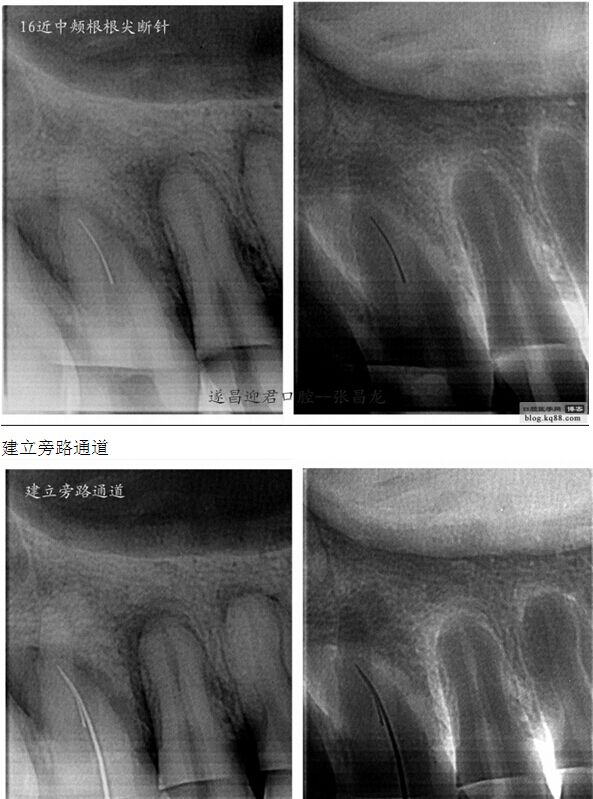

下面是我最近的一個(gè)患者,患者14,15,16均因楔狀缺損導(dǎo)致牙髓壞死,根管治療期間,16的近中頰根發(fā)生了斷針。

每個(gè)牙科醫(yī)生都不愿碰到器械分離,但常在河邊走,哪有不濕鞋的,我想大部分醫(yī)生根管治療中都發(fā)生過(guò)器械分離吧。在此就不在累贅那些造成根管器械分離的原因,醫(yī)生們也都知道那些。遇到器械分離莫慌,我們還是有挽救的余地。由于醫(yī)生的技術(shù)原因,設(shè)備原因,不是每個(gè)斷針都能取出來(lái)的。與對(duì)一部分?jǐn)噌樜覀兛梢試L試建立旁路通道,斷針與根管壁之間的間隙慢慢通入到工作長(zhǎng)度,然后常規(guī)根管治療。